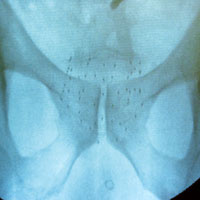

Abb. 2

Durchleuchtungsbild bei der Brachytherapie: Seeds in der Prostata

Die Bestrahlung von aussen hat in den letzten Jahren riesige Fortschritte erzielt. Heute kann die Bestrahlungsdosis sehr genau auf die Prostata gerichtet und somit umliegendes Gewebe geschont werden. Bei der zweiten Form der Strahlentherapie, der Brachytherapie, werden millimetergrosse radioaktive Metallkapseln, sogenannte Seeds in der Prostata positioniert. Diese Therapie wird bei einem noch kleinen und wenig aggressiven Tumor empfohlen. Sie bietet verschiedene Vorteile, insbesondere kann, vergleichend zur Prostataentfernung, die Potenz besser erhalten und die Behandlungsdauer verkürzt werden.